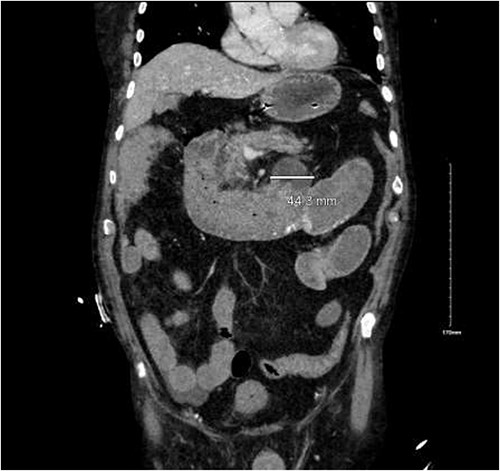

CTA demonstrated angiodysplasia in the duodenal diverticulum at the duodenojejunal junction with associated contrast blush (Figs 1 and 2). The urgent opinion of an interventional radiologist was sought in a tertiary centre. The patient was accepted for urgent embolization in an attempt to stabilize the patient. The patient required an intra-hospital transfer overnight.